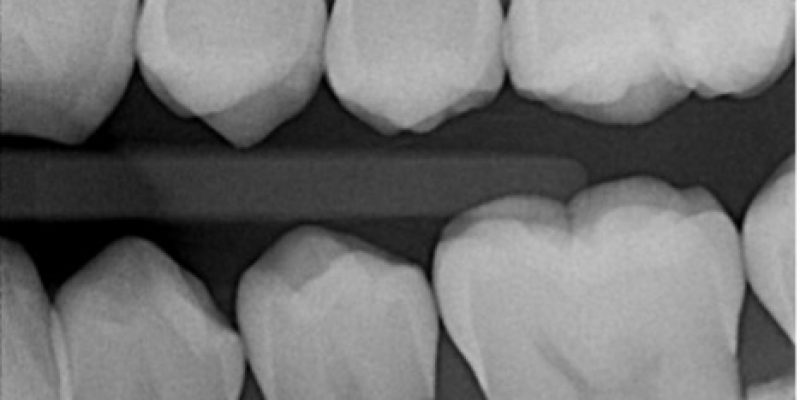

A bitewing intraoral radiograph.